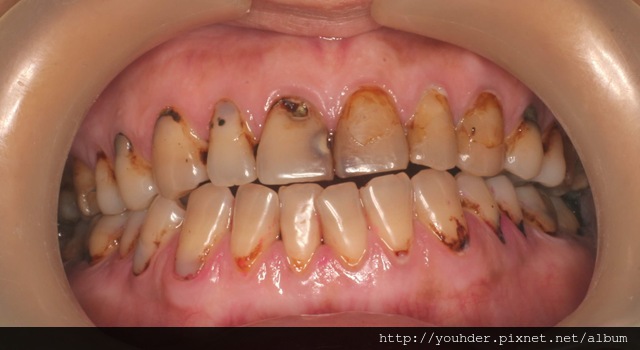

但也有許多患者, 看到的時候,你會懷疑怎麼可以容許自己的牙齒變成這樣?

A) 注意下顎門齒其實補過N次了,但填補速度永遠趕不上蛀牙速度。

B) 上顎正面還可以見人的兩顆牙齒其實是假牙套。

C) 當蛀牙拖到這種程度,許多牙已經面臨拔除的命運,

問題是 才30出頭的人如何負擔的起許多植牙?

而活動假牙對這樣高蛀牙率又年輕的患者實在不是好的選擇。

這位也是才30出頭的患者。他的蛀牙率高並不全然是刷牙的問題,

相反的,患者口腔衛生還算OK。

可以注意到許多牙齒接近牙齦處的牙面都有變色的現象,

是先天齒質不良又缺乏積極的照顧,

才導致許多牙齒蛀到爛牙根需要被拔除的地步。